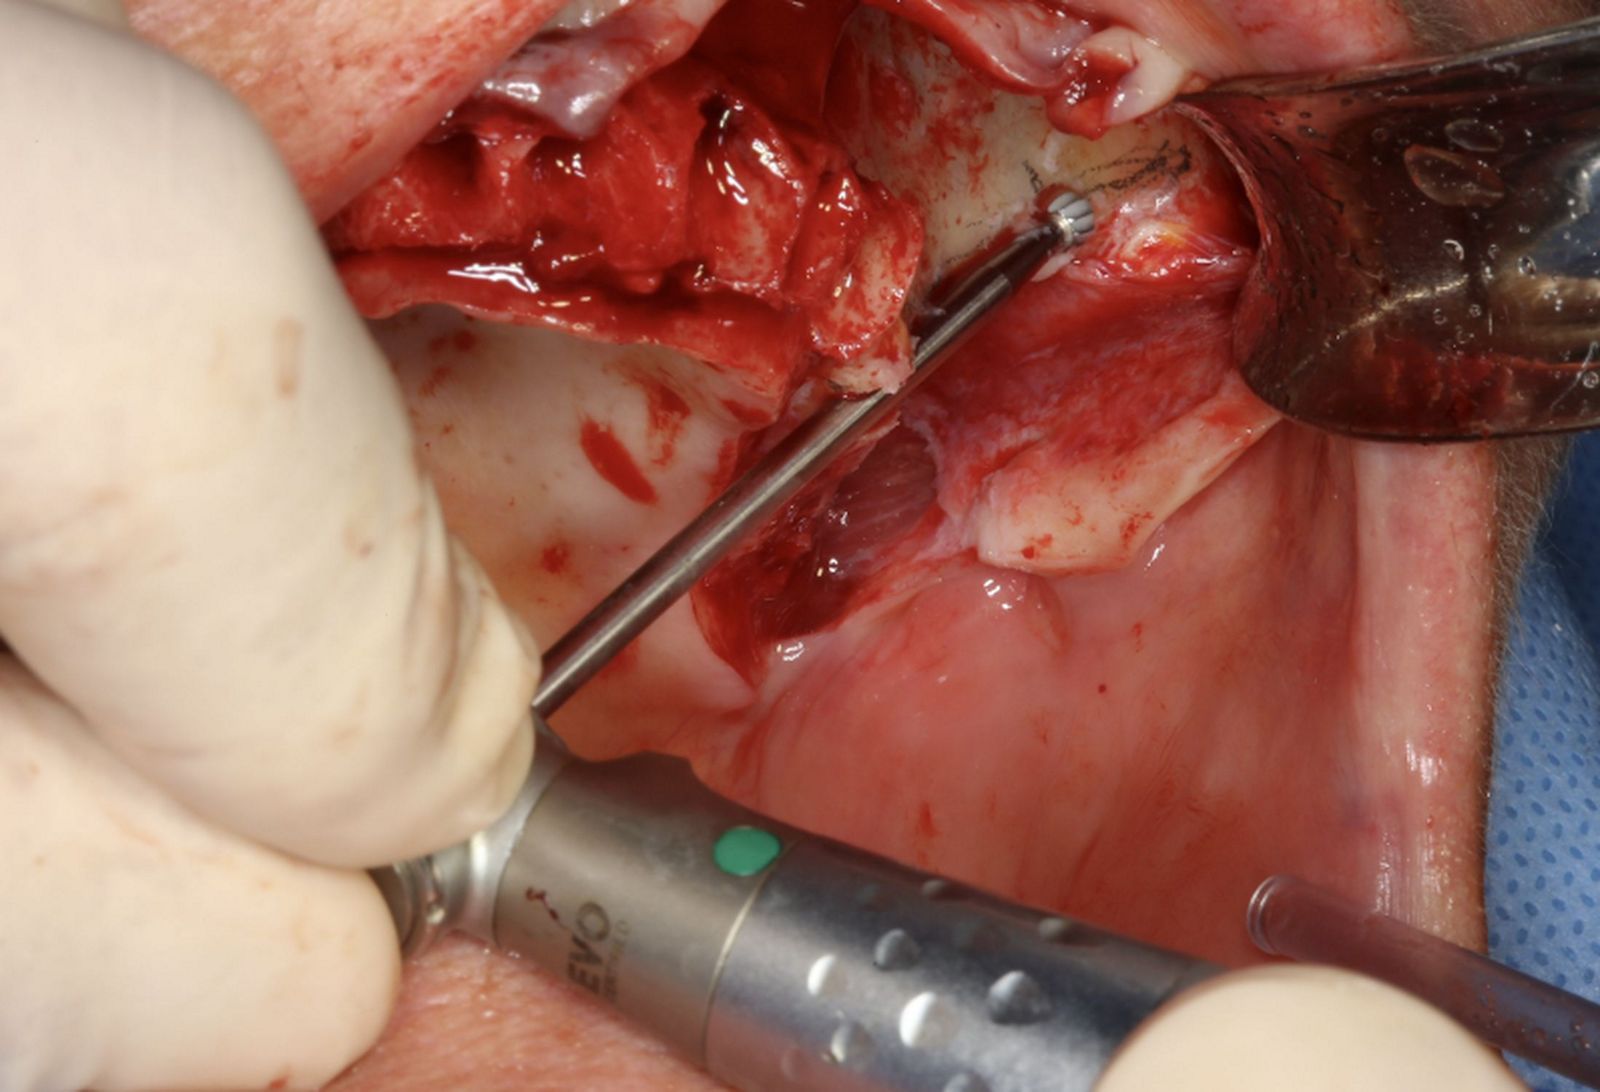

Відкидання м'якотканинного клаптя і маркування точок сверління

Послідовні етапи препарування кісткового ложа під імплантат

Етапи встановлення імплантату Straumann ZAGA Flat